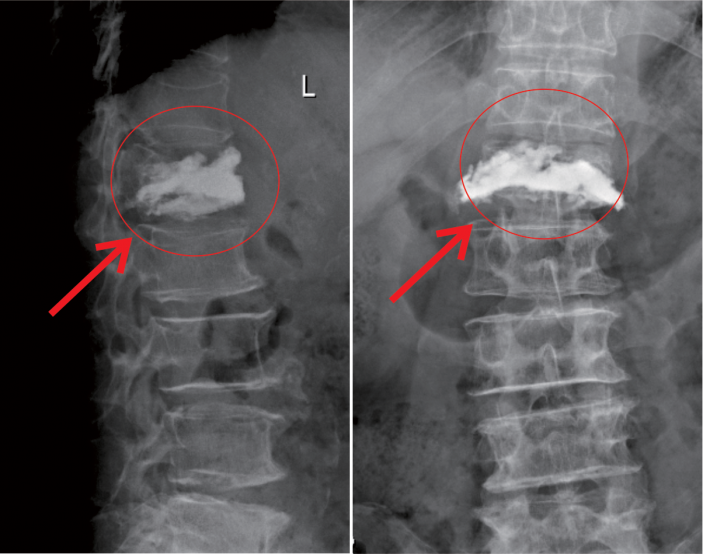

△術前MR顯示,第一腰椎壓縮性骨折

△術後,病變的椎體迅速恢複了功能

在我院先進的術中三維CT引導下,杜教授确定L1雙側椎弓根進針點,娴熟地将穿刺針穿入L1椎體,經穿刺針建立通道将約11ml骨水泥注入坍塌的椎體中。術中監視,注入的骨水泥逐漸支撐起原本壓縮空洞的椎體。骨水泥凝固後,病變的椎體迅速恢複了承重能力。手術持續約40分鍾,開展非常成功,術後老人的疼痛馬上消失,翻身也無疼痛,第二天就能使用助步器下地行走。